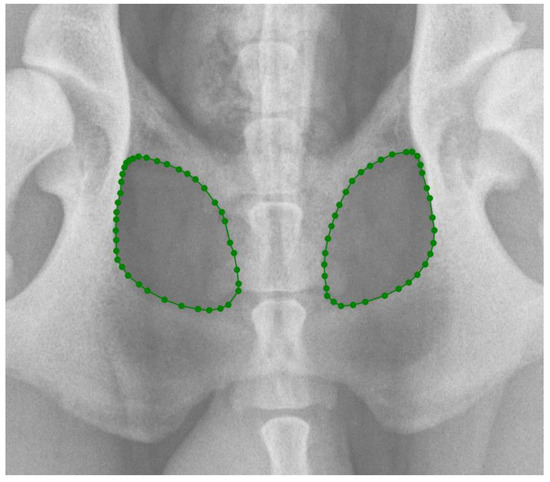

In the first part of the study, 203 radiographs in DICOM format were manually annotated using the polygonal image annotation tool, LabelMe [20], to delineate the right and left obturator foramina. The AIWW was calculated by measuring the widths of the right and left iliac wings in millimeters. A horizontal line was drawn between the dorsal and ventral iliac cortices at the cranial aspect of the sacroiliac joint on both sides (Figure 1). The AIWW was determined by subtracting the width of the right wing from that of the left [10]. The AOFW was calculated by measuring the widths of the right and left obturator foramina in millimeters. A horizontal line was drawn between the medial and lateral aspects of each foramen at its widest points (Figure 1). The AOFW was determined by subtracting the width of the right obturator foramen from that of the left [10]. The AIWW and AOFW, measured in millimeters (x), were used separately to estimate the degrees of pelvic rotation (y) through the following regression equations: y = 0.997x + 0.061 for AIWW and y = 1.644x − 0.912 for AOFW [10]. The AOFA was calculated by measuring the areas of the right and left obturator foramina in square millimeters. For this purpose, the areas were outlined using semantic segmentation, employing pixel-wise labeling to trace the boundaries of both obturator foramina (Figure 2). The AOFA was determined by subtracting the area of the right obturator foramen from that of the left.

Figure 1. Measurement of the widths of the right and left iliac wings (IWW) in millimeters (mm): horizontal lines were drawn between the dorsal and ventral iliac cortices at the cranial aspect of the sacroiliac joint on both sides. Measurement of the widths of the right and left obturator foramina (OFW) in mm: horizontal lines were drawn between the medial and lateral aspects of each foramen at their widest points. Asymmetry was calculated as the difference between the two measurements (largest minus smallest). R indicates the right side.